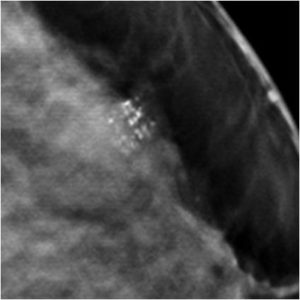

59 Yr old female, referred from outside for suspicious microcalcifications in left breast.